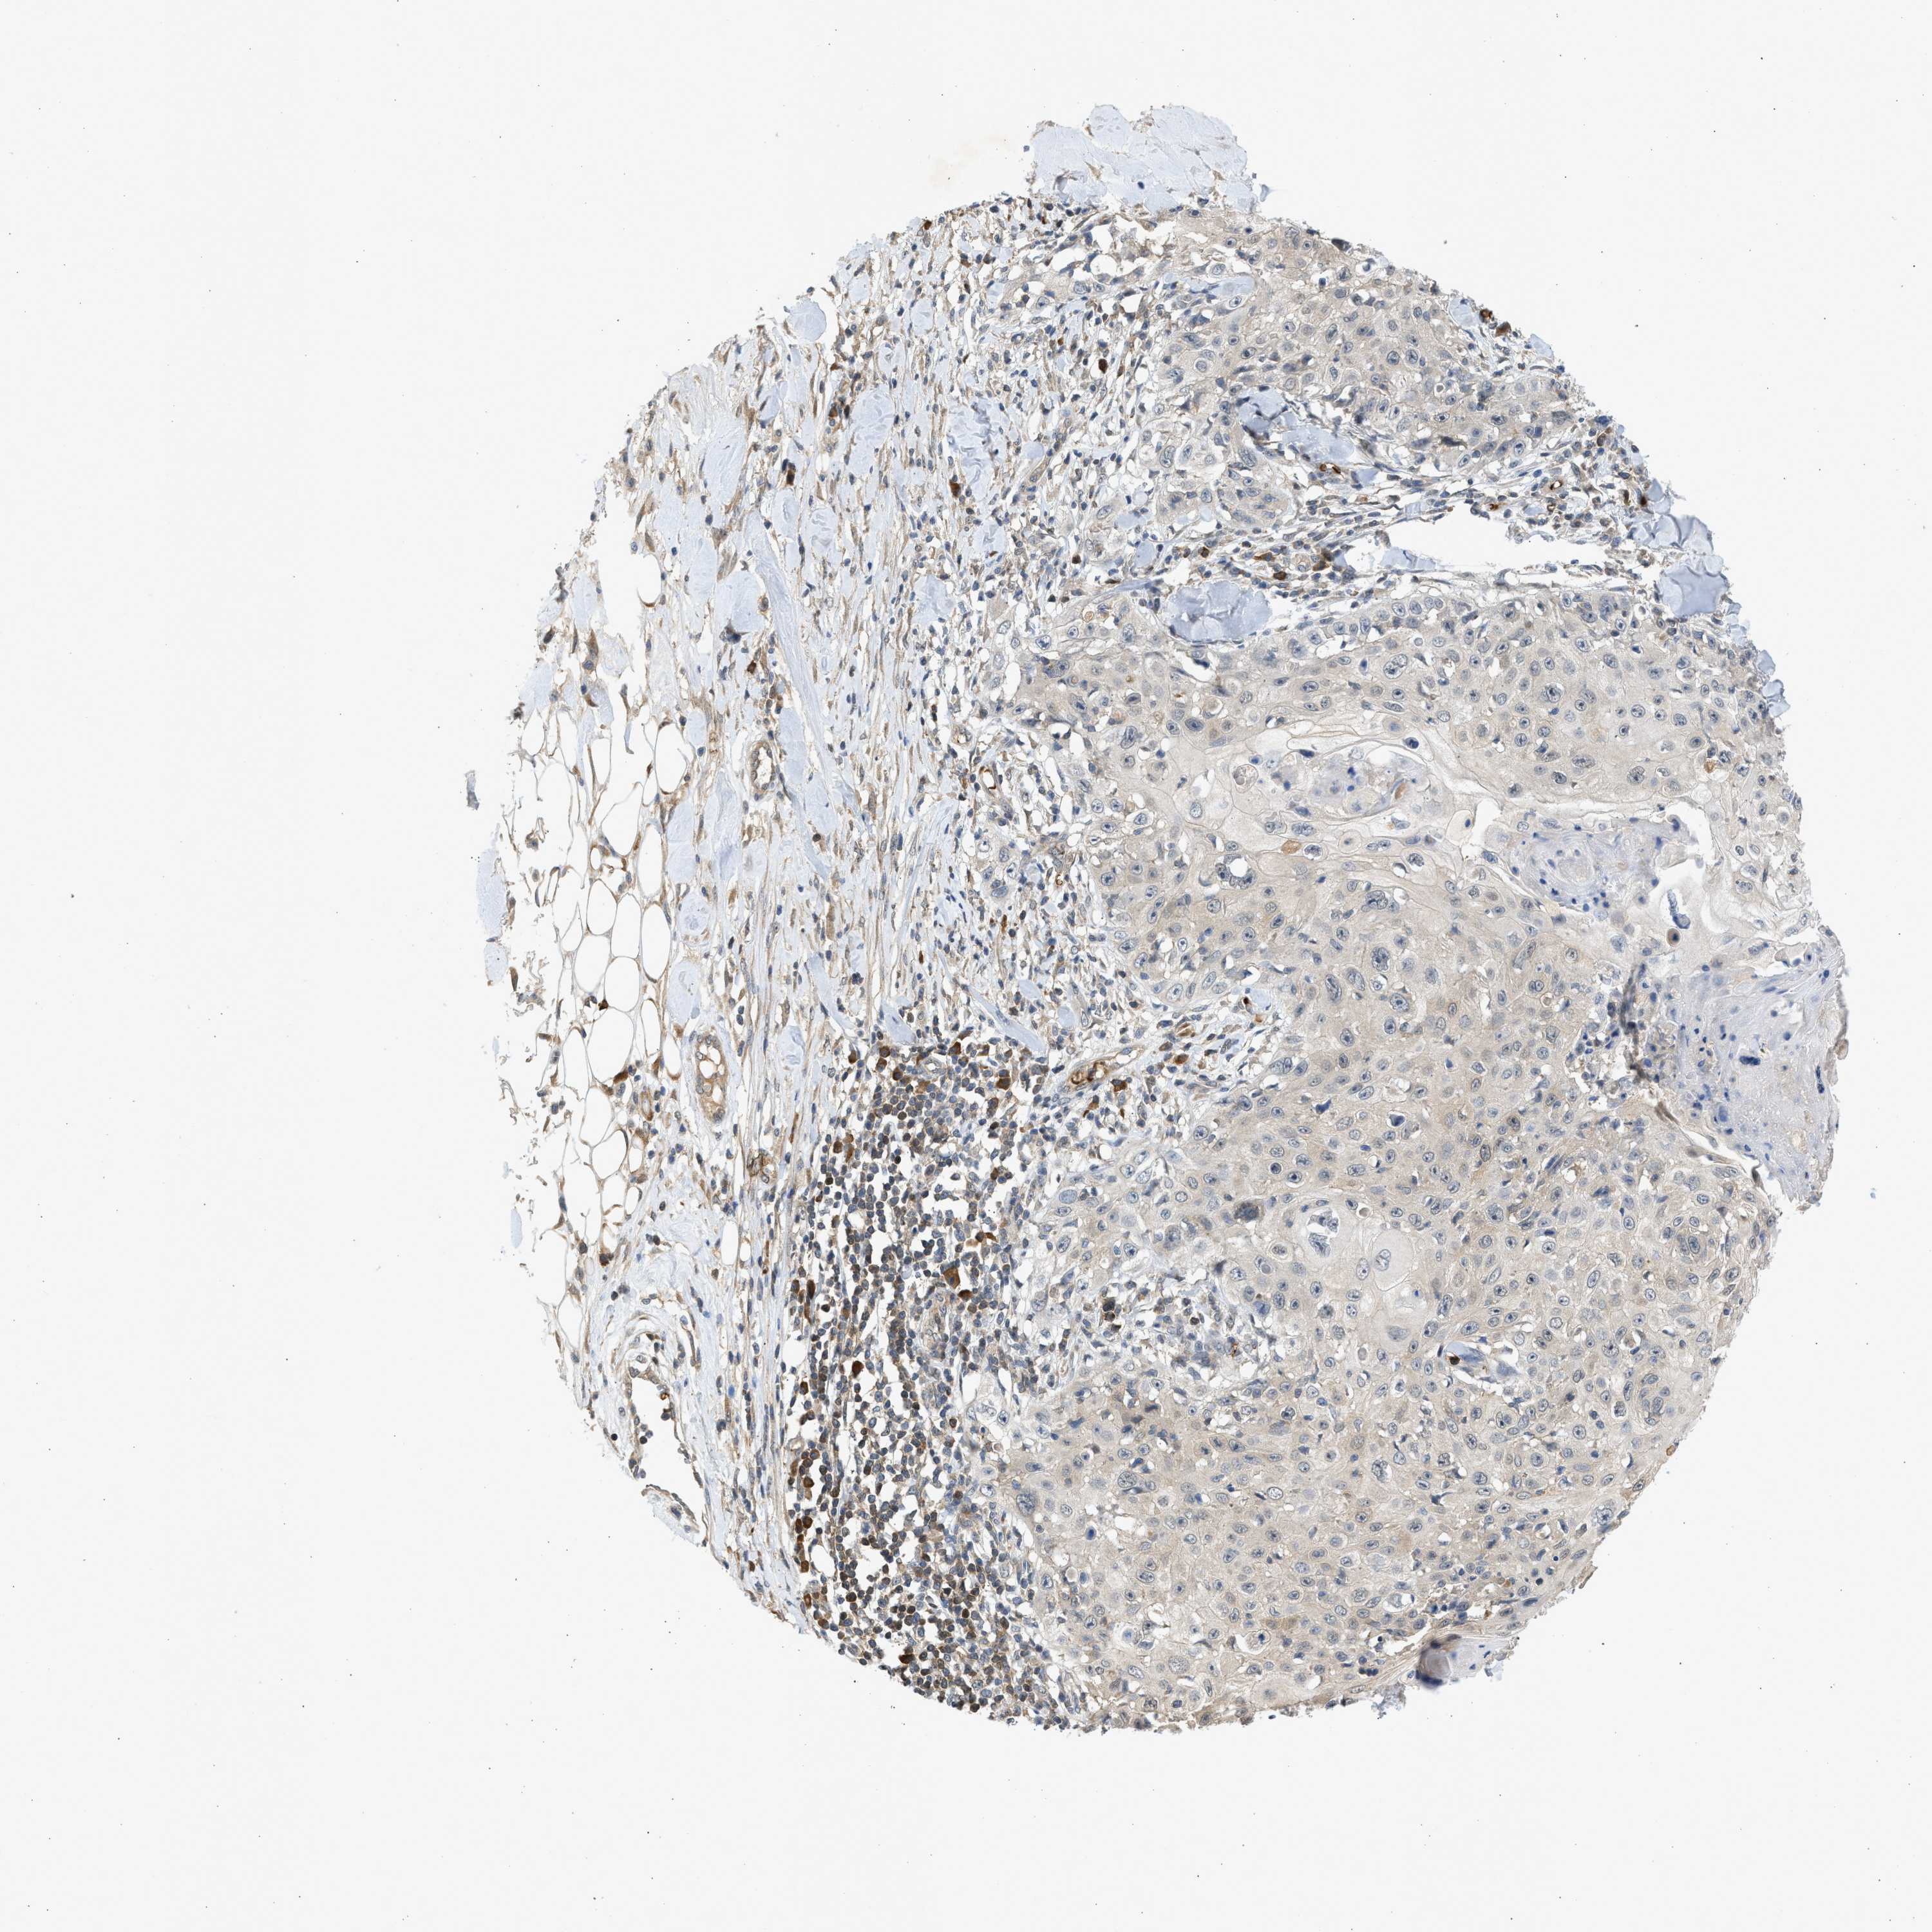

SKIN CANCER - Protein expressioni

A mouse-over function shows sample information and annotation data. Click on an image to view it in a full screen mode. Samples can be filtered based on level of antibody staining by selecting one or several of the following categories: high, medium, low and not detected. The assay and annotation is described here.

Each image is clickable and will lead to virtual microscopy that enables deeper exploration of all samples and also displays staining intensity scores, fraction scores and subcellular localization as well as patient and tissue information for each sample.

Antibody CAB018561

Staining

Medium

Intensity

Moderate

Quantity

75%-25%

Location

Cytoplasmic/membranous

Squamous cell carcinoma, NOS

Squamous cell carcinoma, metastatic, NOS